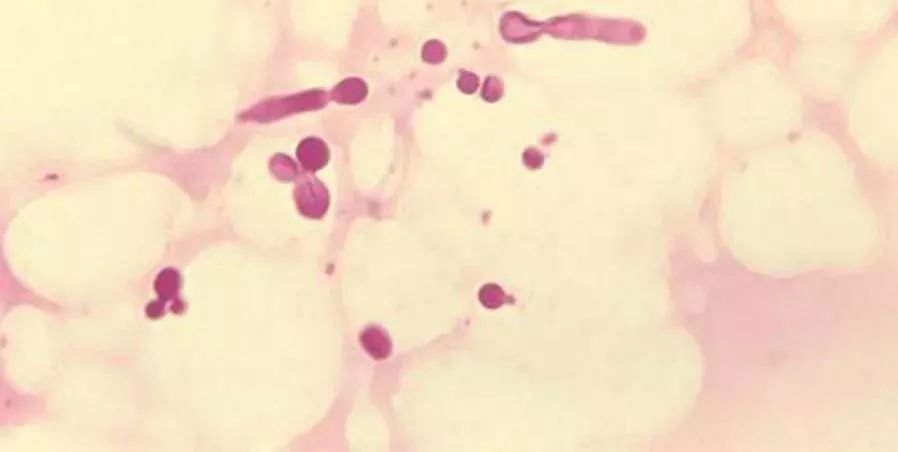

抗真菌:有实验证明,,,乳铁蛋白可以杀死真菌(须癣毛癣菌、、、、白色念珠菌),,,,但是作用机理待研究。。。